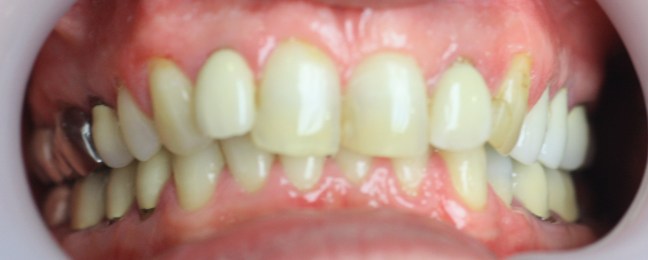

Elsősorban funkcionális kezelés: jobb alsó hiányzó fogak implantátummal történő pótlásával, fordított harapás megszüntetésével, megsüllyedt harapás korrekciójával, összes maradó fog koronázásával.

A választott korona típusa : fémkerámia.

A választott fogszín: A2 .

A protetikai munka elkészülésének ideje: 10 munkanap.